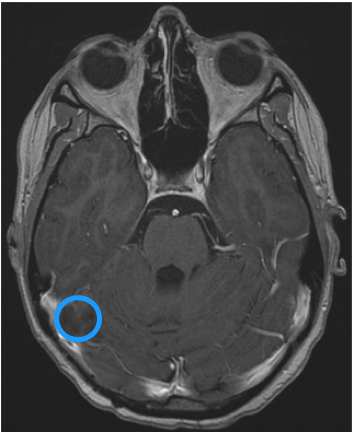

脑积水治疗预后怎么样?脑积水什么时候需要手术?

脑积水是一种过量的脑脊液(CSF)在脑室(含液体的腔)内积聚并可能增加头部压力的疾病。神经外科中比较常见,它的原因多种多样。虽然脑积水常被描述为脑中的水,但水实际上是脑脊液...